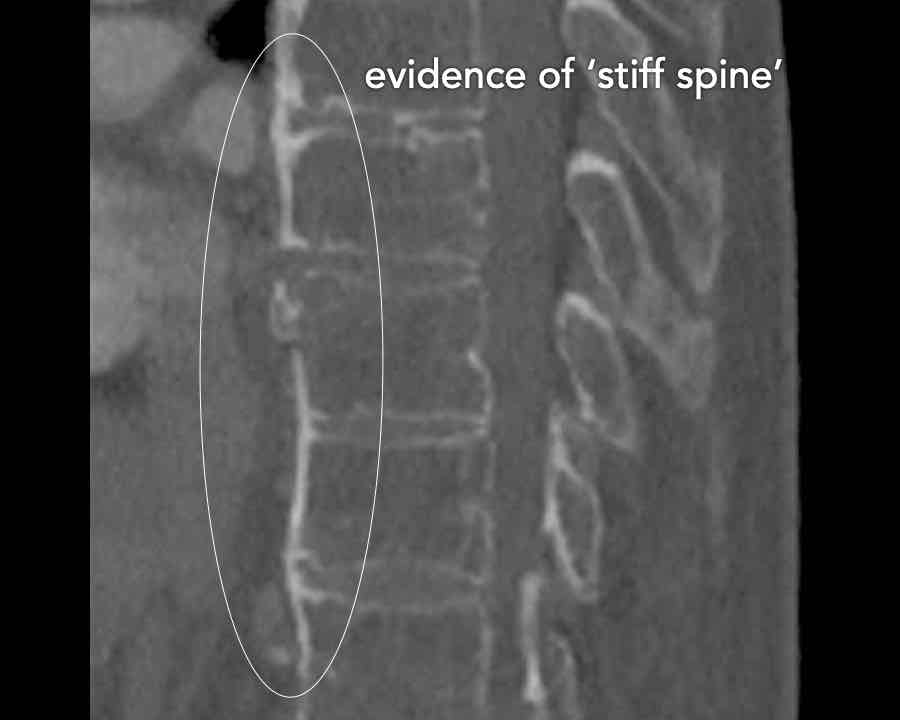

B3 Extension distraction injury

Hyperextension can result in distraction of the anterior tension band, which is formed by the vertebral bodies, the anterior and posterior longitudinal ligaments and the intervertebral disc.

These injuries can be difficult to detect since patients are scanned in the supine position laying on their back, which may obscure the anterior distraction.

However, these injuries mainly occur in patients with a rigid spine as a result of osteoarthritis, DISH or Ankylosing Spondylitis (SpA).

Stay persistent when examining a patient with a rigid spine until you have found the B3 injury.

Scroll through images.

What are the findings?

Findings

- C injury? No.

- Signs of a rigid spine?

Yes (DISH), so a B3 injury is very likely. - A subtle fracture on the anterior vertebral body (arrows).

- No separation, probably due to positioning of patient in the scanner

Conclusion

Injury type B3.